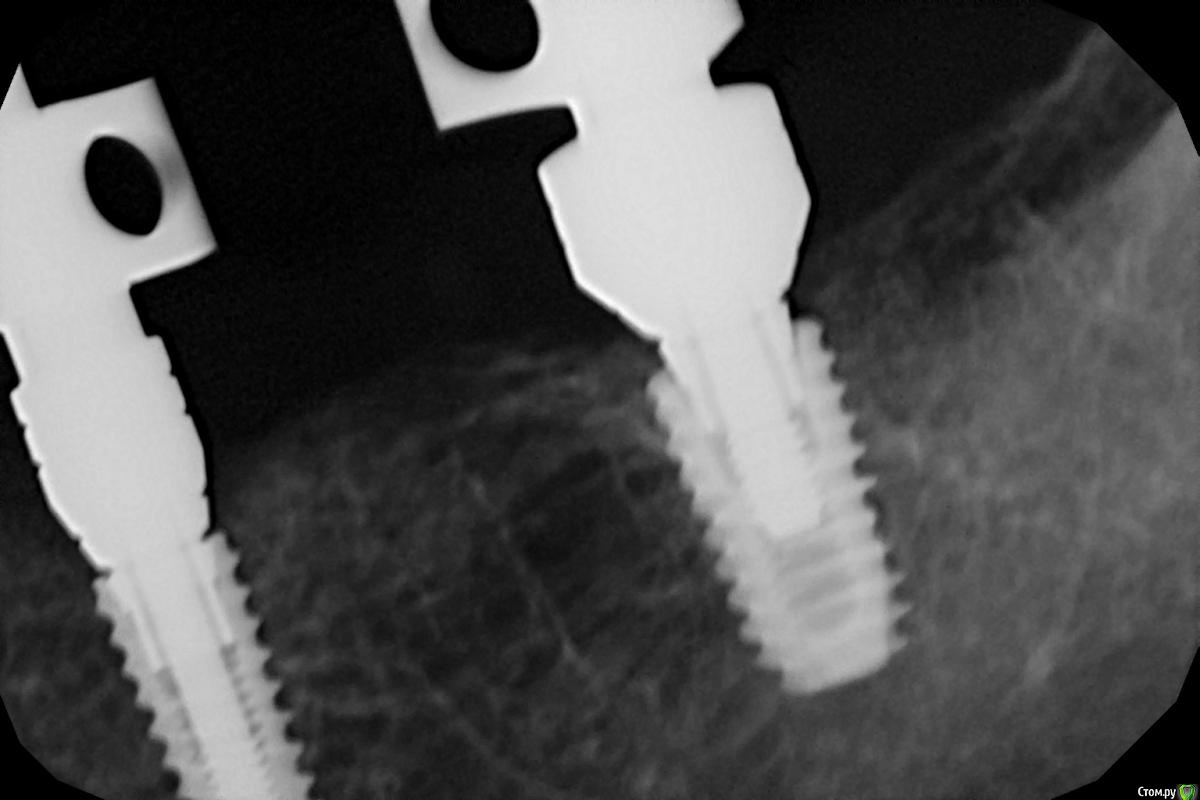

Dman Опубликовано 26 февраля, 2019 Поделиться Опубликовано 26 февраля, 2019 Зачастую это действительно проблема. и для временных коронок тоже нужно снять оттиск. Автору очень рекомендую полистать полный каталог осстема, там есть снимки и описания как и что должно выглядеть. На приложенных снимках трансфер 35 досел, 37 - недосел . Снимок готовой коронки с абатменом, все сидит. Ссылка на комментарий